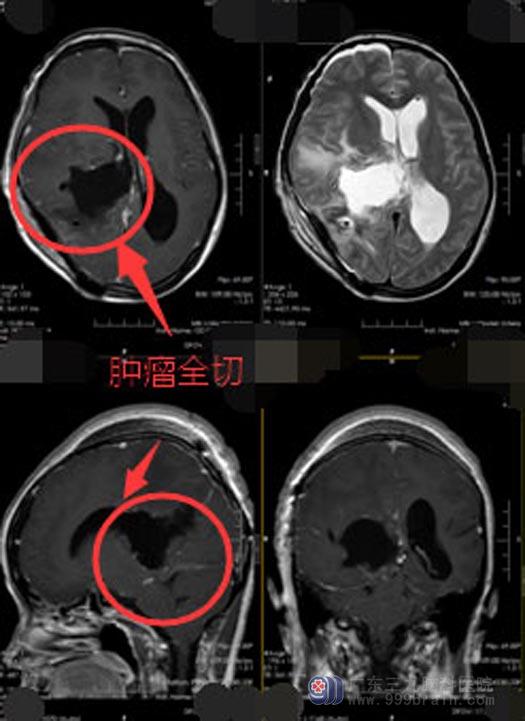

完善术前准备后,由鲁明主刀,在全麻下行“右侧侧脑室巨大脑膜瘤切除+硬脑膜修补+颅骨成形术”。麻醉满意,手术顺利。术后半个月复查头颅CT平扫报告:1. 右侧侧脑室三角区占位效果基本消除;2. 幕上梗阻性脑积水较前基本消除。出院时,小茹恢复正常,没有出现后遗症。